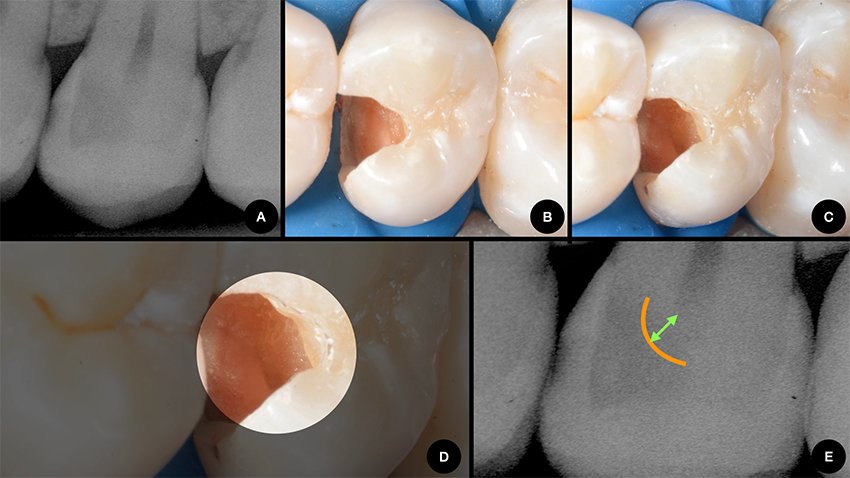

Figure 1: Deep caries lesion restored following the selective removal approach. Clinical pictures were performed in collaboration with Prof. Dr. Rayssa Ferreira Zanatta. A. An asymptomatic, vital tooth that reacted normally to a sensitivity test to cold stimuli, presenting a deep lesion (radiolucency at the inner third/inner fourth of dentin) B. Margins and peripheral walls of the cavity prepared until sound tissue/hard dentin. C. Deepest carious dentin towards the pulp at the cavity floor is preserved to avoid pulp exposure or an excessively thin dentin layer between cavity and pulp. D. In a closer view it is possible to observe the layer of soft carious dentin that was not removed. E. The rationale of selective caries removal is to preserve a layer of dentin at the cavity floor and avoid unnecessary trauma or complications to the pulp that usually occur when all carious dentin is removed. With well-sealed restorations (good adhesive procedures on margins and peripheral walls), any microorganisms left become unviable, and the lesion does not progress.